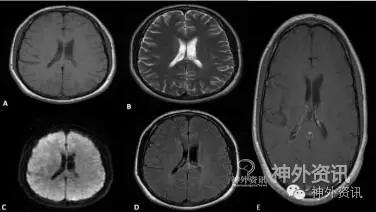

患者无手术并发症,术后恢复良好,头颅CT扫描显示肿瘤全切。随访2.5年,头颅MRI复查未见肿瘤残留和复发(图3)。

图3. 随访头颅MRI轴位像显示,肿瘤完全切除,无残留和复发。